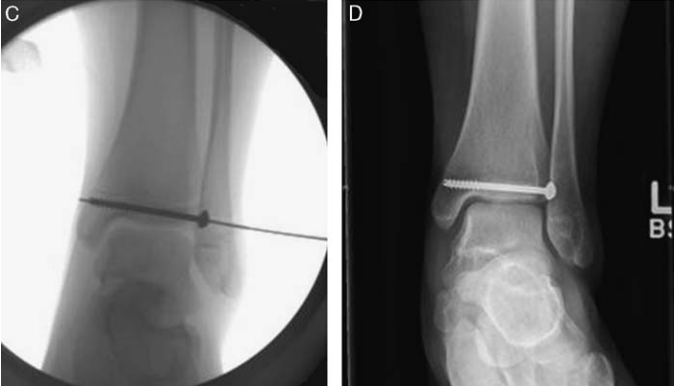

辅助检查上,由于Tillaux骨折片较小、X线片上有胫骨的遮挡以及临床医生认识不足,所以很容易被漏诊。一般来说,正位、侧位和踝穴位 X 片可发现移位超过 2 mm 的 Tillaux 骨折(在踝关节 X 片显示为 Salter-Harris III 型);但如果移位不大,X 片就极易漏诊。临床上对怀疑有该部位损伤时,应摄踝关节内旋30°~45°斜位X线片和CT片,CT 是评估 Tillaux 骨折及其移位程度的最佳术前手段,评估移位不大的 Tillaux 骨折更敏感。

移位 > 2 mm 的骨折需要考虑手术治疗。包括闭合复位经皮克氏针或空心螺钉固定、切开复位内固定、关节镜辅助下复位固定。常见的内固定方式有克氏针和空心螺钉。内固定可跨骺板,因为 Tillaux 骨折常为青少年,骨骼接近成熟,因此穿过骨骺很少会发生双下肢不等长等情况,一般愈后较好。